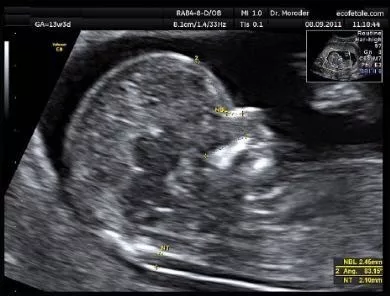

胎儿NT是指在胎儿11周~13周+6天(头臀长应不小于45mm , 及不大于84mm)利用超声检查到的胎儿颈后皮下积液 , 为什么要在这个期间检查呢?11周之前因为胎儿太小 , 而过了14周 , 过多的液体可能被胎儿正在发育的淋巴系统吸收 , 结果不准确 。

超声上是如下图这样的

我的NT是正常范围的哦!